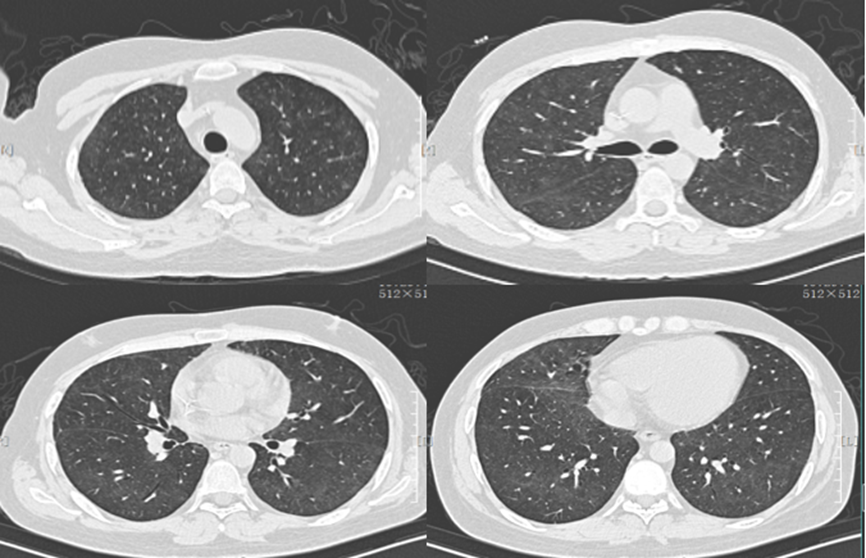

9月21日住院期间再次出现发热,气促明显加重,9月23日复查胸部CT示肺部弥漫性磨玻璃样渗出,双下肺可见实变病灶(图3),再次于全身麻醉下行支气管镜检查,镜下见气管至各叶段支气管黏膜充血水肿,触之易出血,腔内可见脓性及黏液性分泌物,予以吸出,左肺下叶行支气管肺泡灌洗,灌洗液细胞学结果示:外观淡血性,微浊。有核细胞计数520×106/L(↑),淋巴细胞占12.00%(↑),多核细胞占80%,特殊染色未查到耶氏肺孢子菌滋养体及包囊,可见大量革兰氏阴性杆菌,少许革兰氏阳性球菌,未见真菌孢子和菌丝,培养见肺炎克雷伯菌重度生长(++++),考虑合并肺炎克雷伯菌感染,根据药敏结果加用头孢哌酮舒巴坦3.0 ivgtt q8h 抗菌治疗,体温逐渐下降。

图片

图3  患者胸部CT(2018年9月23日)